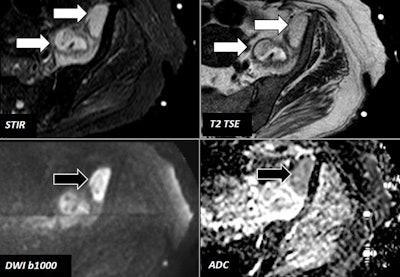

78-year-old woman with fever and left hip pain. MRI identified two loculated lesions at the left psoas muscle (white arrows). Both lesions showed restriction of water diffusion, but the lesion located in the vicinity of the anterior-superior iliac margin (black arrows) demonstrated a higher degree of water diffusion -- data used to select the target lesion for fine-needle aspiration. Soft-tissue abscesses were demonstrated by fine-needle aspiration. All images courtesy of Dr. Teodoro Martín Noguerol.DWI, DCE-MRI, and MRS can provide valuable information about physiopathological features of soft-tissue musculoskeletal (MSK) lesions that allows radiologists to increase the overall accuracy of their studies -- even adding data about the likelihood of response to treatment, lesion recurrence, and early response to chemotherapy or radiotherapy, the authors pointed out.